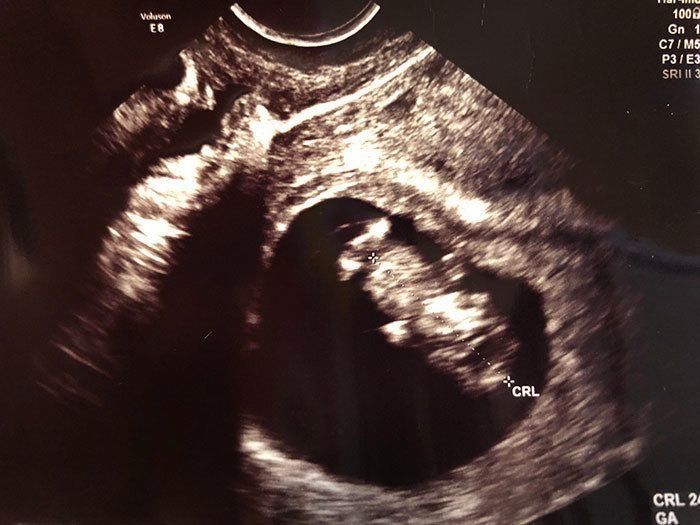

妊娠9週目 丸い胎嚢が、あっと言う間に人のカタチに!

前回のエコーには、丸い袋しか映っていなかった記憶があるのですが、妊娠9週目のエコーでは、もうすでに赤ちゃんの姿になって映っていました! 手足をばたつかせて泳ぐ姿がかわいくて感極まり、思わず涙が…。そして私はこの日、「私が守ってあげなくちゃ!」と、強く思ったのでした。